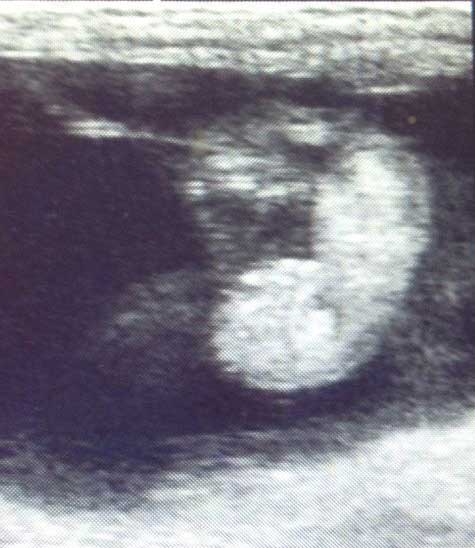

Der richtige Zeitpunkt für eine Trächtigkeitsuntersuchung mittels Ultraschall ist am 14.-16. Tag nach der Ovulation, denn dann ist der Ausschluss einer Zwillingsträchtigkeit am sichersten möglich. Diese ist beim Pferd unerwünscht, da sie sehr häufig bedeutet, dass beide Fohlen oder die Stute nicht überleben. Die zweite Kontrolle erfolgt um den 30. Trächtigkeitstag. Dann kann man bereits eine Frucht mit Herzschlag darstellen. Eine weitere Kontrolle sollte um den 100. Trächtigkeitstag herum erfolgen, da sich die Hormonproduktion dann umstellt.